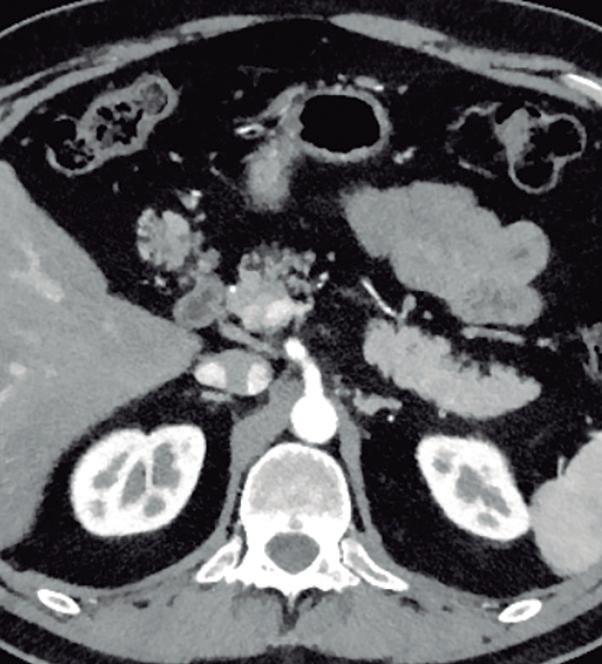

Más allá del diagnóstico de esta anomalía debemos buscar signos imagenológicos indirectos de obstrucción gastrointestinal, como son la dilatación gástrica y de la 1° porción duodenal (Figura 10), con estrechez de la luz del duodeno en el sitio por donde transcurre a través del páncreas anular.18,19

A) Tomografía computada con contraste, plano coronal. El páncreas anular (flecha) provoca dilatación de la 1° porción del duodeno (cabezas de flecha). B) Tomografía computada con contraste, plano axial. Flechas: páncreas anular. Cabeza de flecha: duodeno. C) Tomografía computada con contraste, plano axial, corte más caudal que el previo. Flechas: páncreas anular.

Figura 10. Páncreas anular con obstrucción del tracto de salida gastrointestinal